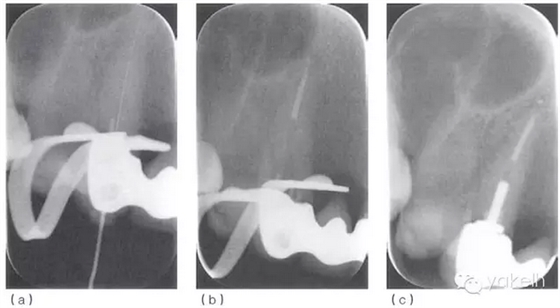

¤¤使用根尖定位儀確定根管的工作長(zhǎng)度,拍攝X線(xiàn)片(圖 5.2.2a)加以驗(yàn)證。采用化學(xué)-機(jī)械方法進(jìn)行完善的根管預(yù)備后,使用牙膠和根管封閉劑,采用熱垂直加壓技術(shù)進(jìn)行根管充填(圖5.2.2b,c)。1個(gè)月后復(fù)診,患者無(wú)癥狀,潰瘍變小,僅黏膜表面遺留瘢痕(圖 5.2.3)。

圖 5.2.2(a)13確定工作長(zhǎng)度的X線(xiàn)片。(b)13根管充填中X線(xiàn)片。(c)13根管充填后X線(xiàn)片。